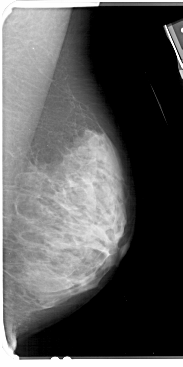

A_1353_1.RIGHT_MLO

RIGHT_MLO LINES 5491 PIXELS_PER_LINE 2731 BITS_PER_PIXEL 12 RESOLUTION 43.5 NON_OVERLAY